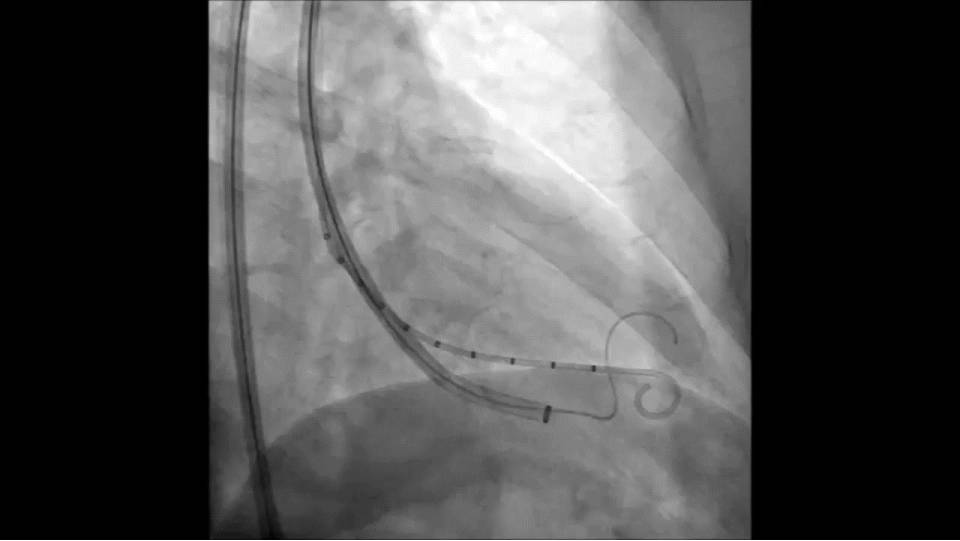

右侧股动脉置入16F鞘管,6FPigtail导管进入左心室,沿猪尾巴置入强生cordis加硬导丝;

沿导丝将16F指引导管置入心尖部;

沿指引导管置入Parachute,左室造影与心超检查位置。

手术过程指引导管到达左心室:

手术过程隔离装置的脚到位:

手术过程充盈球囊:

手术过程装置到位后重复左心室造影: